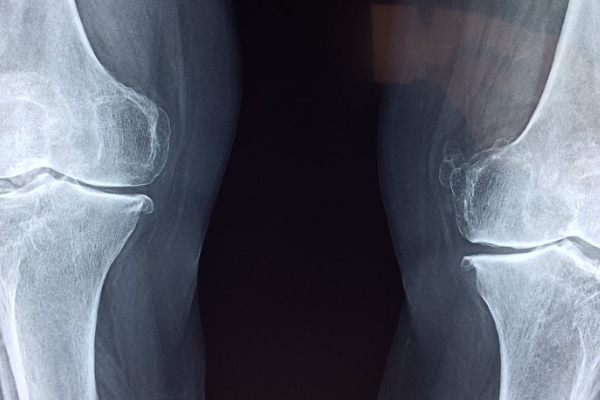

퇴행성 관절염은 관절을 보호하고 있는 연골의 점진적인 손상이나 퇴행성 변화로 인해 관절을 이루는 뼈와 인대 등에 손상이 일어나서 염증과 통증이 생기는 질환으로, 관절의 염증성 질환 중 가장 높은 빈도를 보입니다.

통증은 초기에는 해당 관절을 움직일 때 심해지는 양상을 보이다가 병이 진행되면 움직임 여부에 관계없이 지속적으로 나타나기도 하는데요. 관절 운동 범위의 감소, 종창(부종), 관절 주위의 압통이 나타나며 관절 연골의 소실과 변성에 의해 관절면이 불규칙해지면 관절 운동 시 마찰음이 느껴질 수도 있다고 합니다.

관절은 사용할수록 소모되는 것이기 때문에 노화가 진행됨에 따라 자연스럽게 약해질 수밖에 없는데요. 나이가 들면서 근육이 탄력을 잃고, 크기와 강도가 줄어들면서 무릎에서 나는 소리가 더 많이 발생한다고 합니다. 또 힘줄에도 변화가 생겨 조직들이 뼈와 접촉해 소리가 더 심해질 수 있습니다.